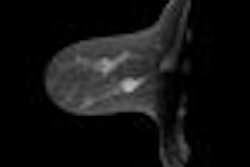

KBCT is a fully integrated, dedicated breast CT scanner designed to image an entire breast with high spatial and contrast resolution at a radiation dose similar to or less than that of mammography. It is designed to eliminate tissue overlap and superimposition of structures, which potentially can lead to an inability to diagnose breast cancer early.

The system can acquire a set of images in 10 seconds, creating 3D images and multiplanar cross-sectional slices.